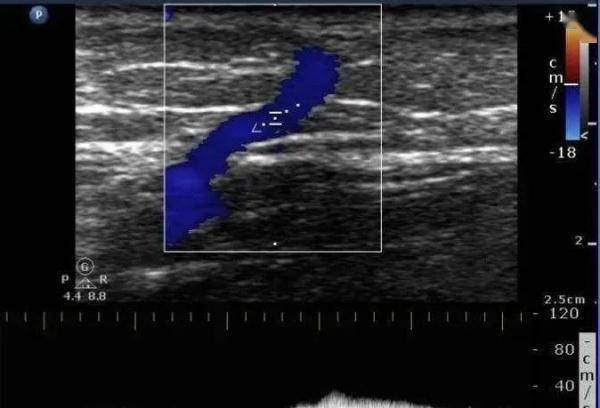

最终 , 通过B超、血流动力学等专科仔细检查 , 孟路阳找到了隐藏在皮肤下的已经曲张的静脉 。

文章图片